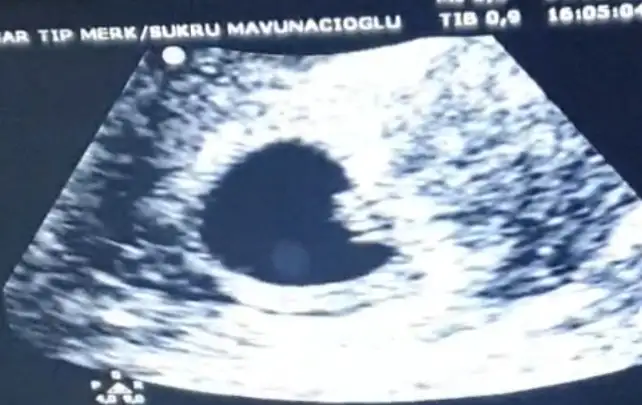

İlk koyduğum ultrason vajinal 5 haftalık, ikincisi görüntü kalitesi daha düşük olan karından 6 haftalık 🥰

• 747FCF6B-325E-4BF7-B5DA-5C3BB6168B83.webp

747FCF6B-325E-4BF7-B5DA-5C3BB6168B83.webp

28,1 KB · Görüntüleme: 278

• 39A6A9E6-5DA9-4813-B2FE-70C636DF5AA5.webp

39A6A9E6-5DA9-4813-B2FE-70C636DF5AA5.webp

18,7 KB · Görüntüleme: 263